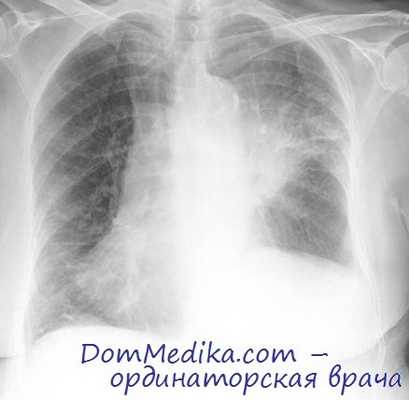

Компьютерная томография рака легкого

КТ — основной метод визуализации при диагностике рака легкого после выполнения рентгенографии органов грудной клетки в прямой проекции. Всем пациентам, за исключением агонирующих, следует провести КТ органов грудной клетки верхних отделов брюшной полости с контрастным усилением. Описание КТ необходимо учитывать при определении стадии заболевания.

КТ следует выполнить при первой же возможности, до каких-либо инвазивных процедур. Это нужно для сокращения методов диагностики, получая от них (например, от бронхоскопии) максимальную пользу.